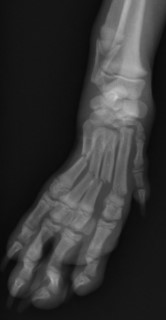

手術前 手術後

ピンニングで整復しました。